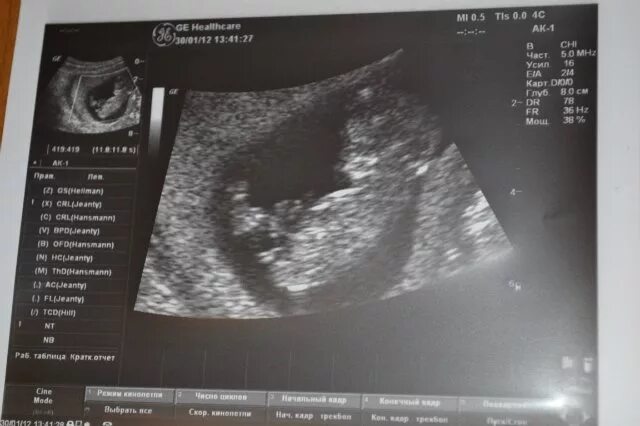

Узи 6 месяцев